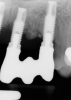

Given patient concerns about radiation exposure, it is important to know how, when, and why radiographs should be taken. Although there are concerns about radiation, radiographs make it possible to determine bone levels at baseline—ie, at implant and restoration insertion—and to monitor them over time. Vertical radiographs should be as parallel as possible to the implant body, so that the implant threads are clearly visible. Typically, periapicals should be taken once a year around dental implants. Figure 3 and Figure 4 shows bone loss up to the fifth and sixth thread.

Radiographs showing bone loss around an implant.

Figure 3

Figure 4